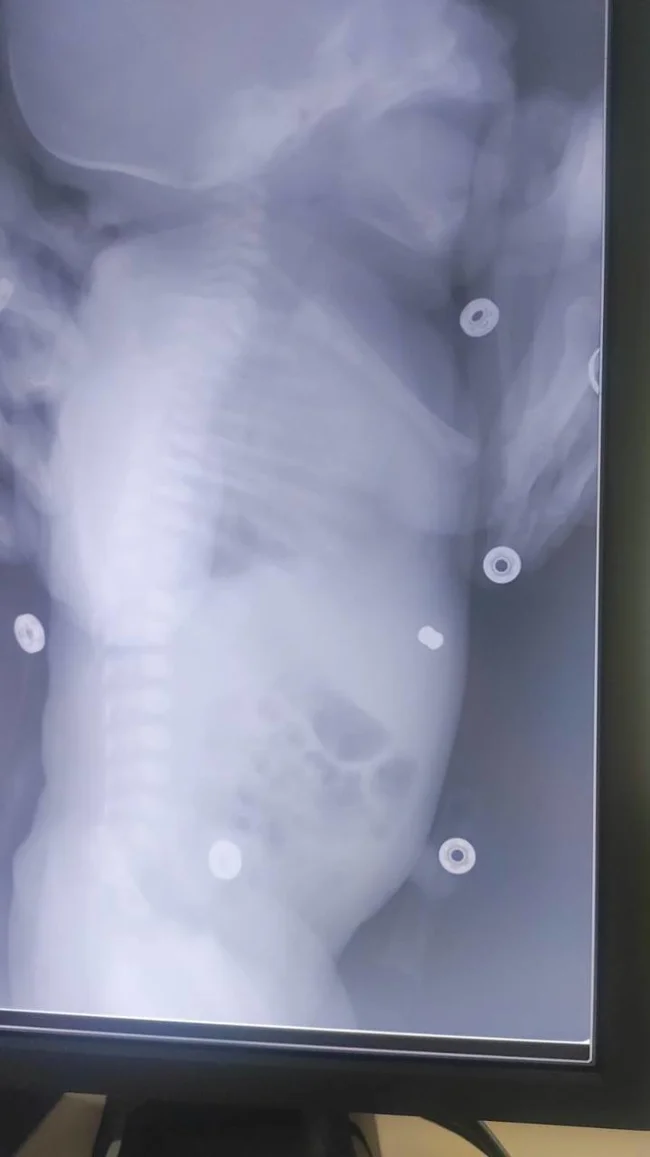

Якось майбутній тато тренувався на задньому дворі та стріляв по мішенях із пневматичної зброї. Несподівано він схибив і випадково потрапив вагітній дружині прямо в живіт. УЗД показало, що куля застрягла у плода в животі, але знаходилася у дитини під шкірою та особливих страждань, не завдавала.

Небезпеки для життя ні матері, ні дитини стороннє тіло не завдавало.

Лікарі вирішили не оперувати жінку, яка на той момент перебувала на 30-му тижні вагітності. Вона спокійно доходила до потрібного терміну та народила малюка. Після народження дитину позбавили кулі.